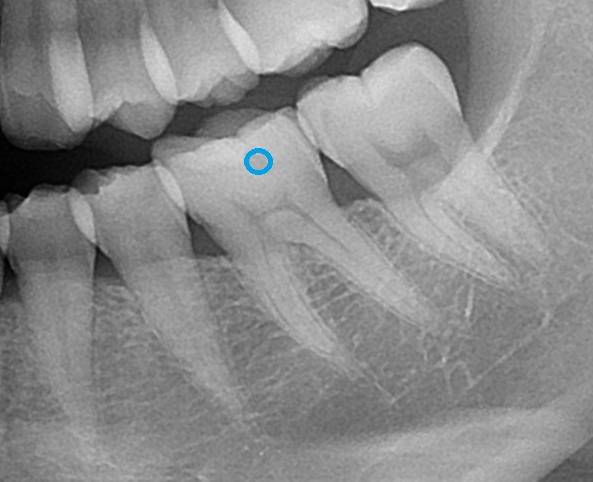

エックス線検査(レントゲン写真)で内部を見てみると、

このような状態です。よくよく見てみると、黒く抜けた影が見えます。

ここですね。

虫歯になると歯の内部が溶けてきます。レントゲン写真で黒い影が出てくるので、虫歯があると分かります。